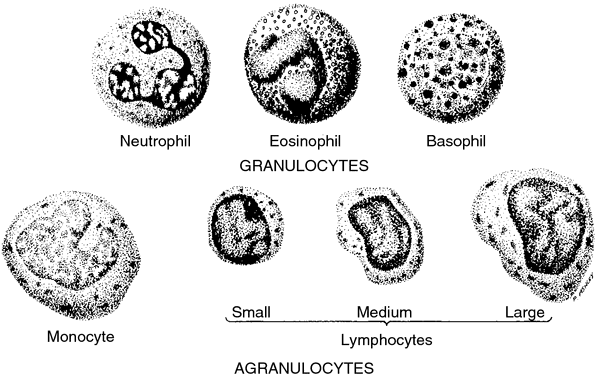

leukocytes